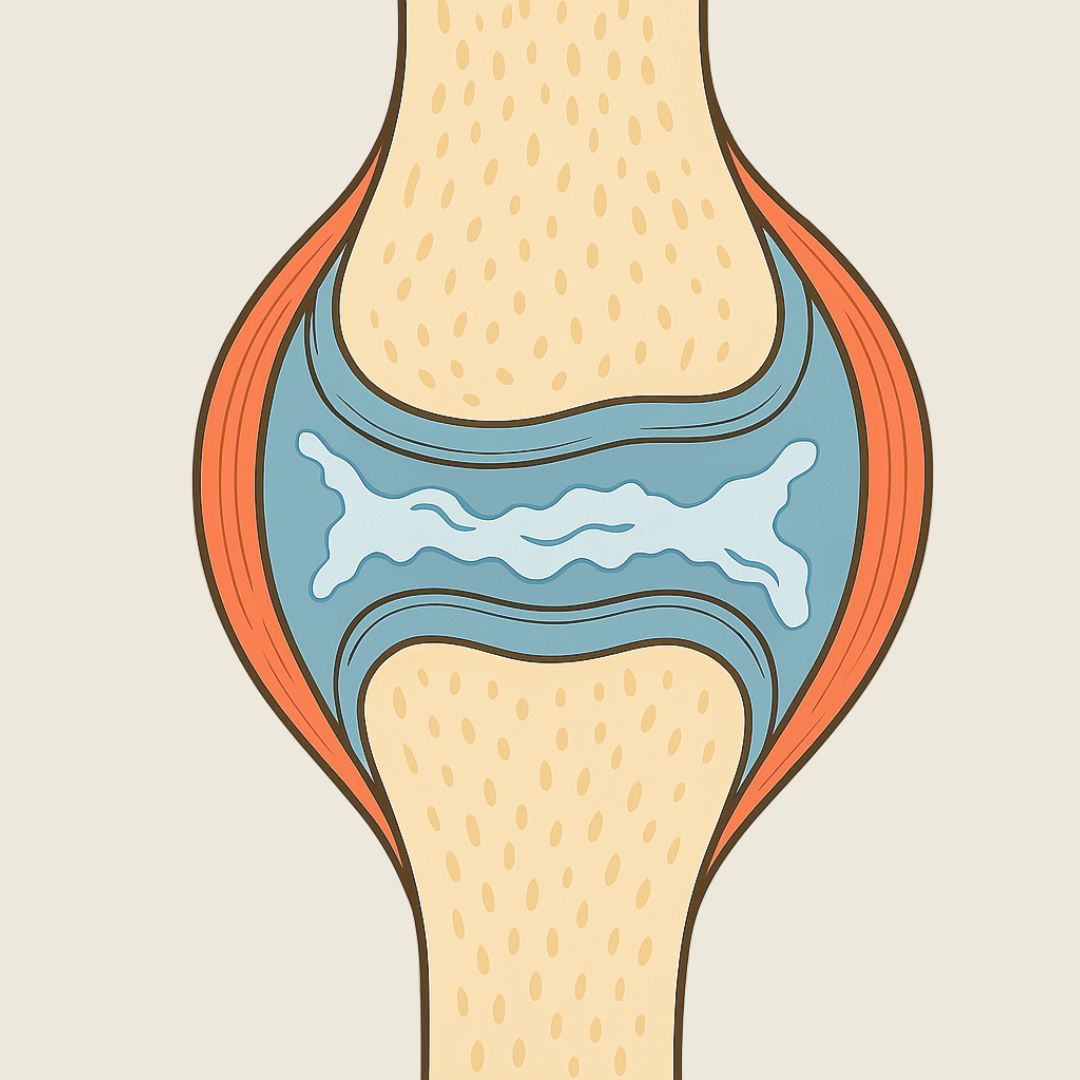

Cartilage Wears Away

The smooth layer that cushions the bones starts to thin and crack, losing its ability to absorb shock.

How Billie's helps: Contains key ingredients like glucosamine and chondroitin, which actively support cartilage regeneration and maintain joint cushioning.

Joint Fluid Becomes Less Effective

The lubricating fluid inside the joint becomes thinner and less protective, reducing its ability to prevent friction.

How Billie's helps: Formulated with essential nutrients that help maintain joint fluid quality, ensuring smoother joint movement and reduced friction.